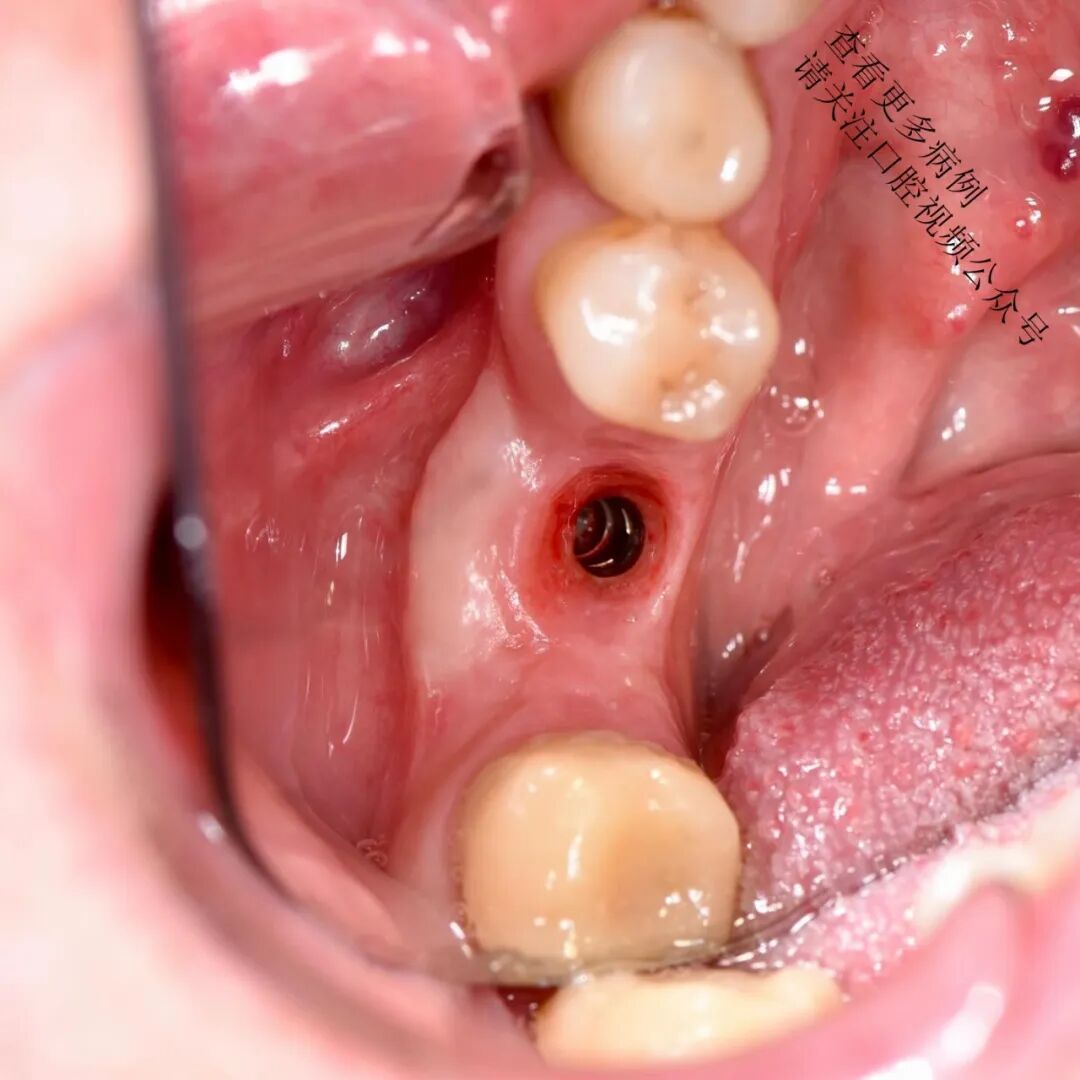

根向复位瓣术

翻制半厚瓣,去除肌肉纤维牵拉

将可移动黏膜固定至根方骨膜(使用6/0单丝缝线,如Monocryl)

术后4个月复查